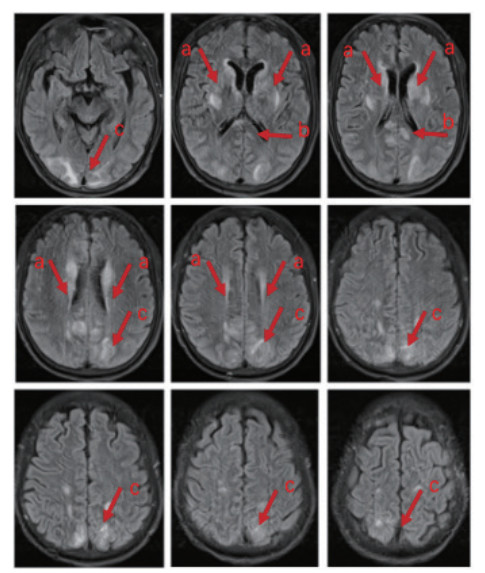

全程镇痛镇静,并行神经营养治疗(醒脑静针、甲钴胺针、四己糖神经节苷脂针、安宫牛黄丸)。第5天可呼唤睁眼,无遵嘱动作及四肢活动。第8天自主睁眼,仍无遵嘱表现,刺痛下肢屈曲,成功脱机拔管。第10天头颅MRI示“两侧基底节区、侧脑室旁、顶枕叶及胼胝体压部异常信号影,脑白质疏松,FazekasⅡ级”(图 2)。第13天自主睁眼,仍无遵嘱表现,发单音,刺痛定位,偶有自主活动,后行高压氧治疗。

| 注: 箭头a所指区域显示基底节区及侧脑室旁存在异常高信号影, 箭头b所指区域显示胼胝体存在异常高信号影, 箭头c所指区域显示枕叶顶叶存在异常高信号影 图 2 患者的头颅核磁共振影像 |

患者入院后持续昏迷,多次头颅CT检查未见异常。入院第10天,MRI显示双侧基底节、顶枕区及胼胝体压部异常信号,并伴脑白质病变。经治疗,患者意识逐步恢复,出院时GCS评分为E4、T2、M5,但仍存在明显意识内容障碍。研究表明,单氰胺中毒患者中73% 发生中至重度意识障碍(GCS < 13),其中80% 头颅CT正常,仅20% 出现不同程度脑水肿。严重脑水肿(≥ 4级)MRI影像常见双侧额叶、枕叶、脑室周围及深部白质信号异常,与本例MRI结果相符[11]。单氰胺中毒导致脑病的确切机制仍不明确,研究提示其可能与细胞缺氧应激反应相关。缺氧诱导因子-1α(HIF-1α)水平与GCS评分呈显著负相关,表明HIF-1α可能在单氰胺相关脑病的发生中起关键作用[11]。